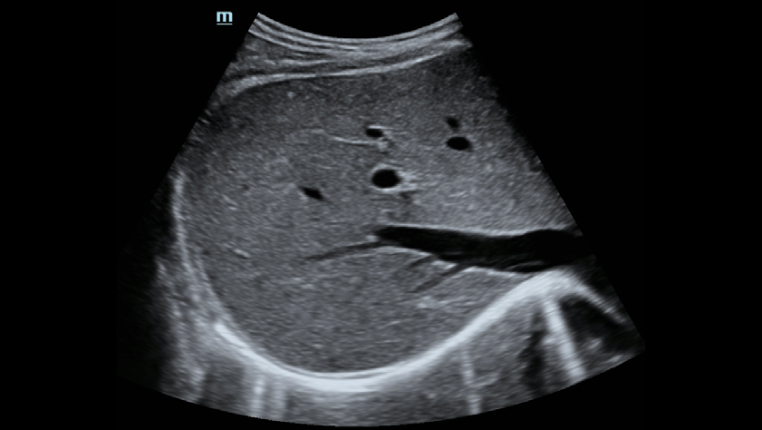

Hepatus ???

? ??? ?? ???? ???? ?? ???? Hepatus? ? ??? ??? ???? ??? ??? ?????. ???? ????? ??? ? ?? ??? ???? ????? ? ?? ???? ? ?? ??? ??? ??? ?????.

??? ???? ?? ? ??? ? ? ???? ?? ??, ??, ???? ? ?? ??? ??? ? ????. ?? ?? ???? ?????.

- ????? ??? ??

- ???? ? ??

- ?? B? ??

- ?? C? ??

- ??? ?? ? ??

- ?? ?? ? ??

- ?? ??

* Hepatus 6?? ?? ??